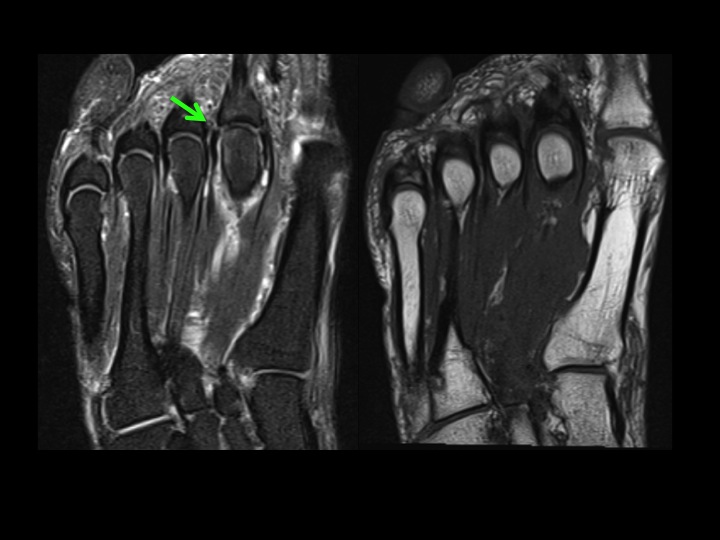

There is flattening of the dorsolateral 2nd MT head (white arrow) with subchondral marrow edema; minimal marrow edema at the base of the 2nd toe (yellow arrow) but not DJD. There is a subtle tear at the midline and lateral paracentral insertion of the plantar plate (red arrows). The tear is near the capsular recess, which is not wide, but there is fluid signal communicating between the MTPJ and the flexor tendon sheath (blue arrow 2nd slide) which is pathologic. 3rd slide shows lateral capsule tear. Ive seen this combo before: Freibergs and PP tear. Makes me think about meniscal root tear and what was formerly-known-as-SONK, and wonder whether it is the Freibergs that leads to the PP/capsule tear or vice versa. Thoughts?

Freibergs Infraction with 2nd MTPJ plantar plate and lateral capsule tear